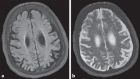

Mutations in NHE6 (also termed SLC9A6) cause the X-linked neurological disorder Christianson syndrome (CS) in males. The purpose of this study was to examine the phenotypic spectrum of female carriers of NHE6 mutations. Twenty female carriers from 9 pedigrees were enrolled, ranging from approximately age 2 to 65. A subset of female carriers was assessed using standardized neuropsychological measures. Also, the association of NHE6 expression with markers of brain age was evaluated using 740 participants in the Religious Orders Study (ROS) and Rush Memory and Aging Project (MAP). A majority, but not all, female carriers demonstrated a deficit in at least one neurocognitive domain (85%). A recognizable neuropsychological profile emerged, revealing impairments in visuospatial function, attention, and executive function. Common neuropsychiatric diagnoses included: intellectual disability/developmental delay (20%), learning difficulties (31%), speech/language delays (30%), and attention-deficit/hyperactivity disorder (20%). Notable neurological diagnoses in aging CS female carriers include corticobasal degeneration and atypical parkinsonism. In postmortem brains from the ROS/MAP dataset of normal and pathological aging, decreased NHE6 expression was correlated with greater tau deposition. Our study provides an examination of the phenotypic range in female carriers of NHE6 mutations. The findings indicate that NHE6-related disease in females represents a new neurogenetic condition.